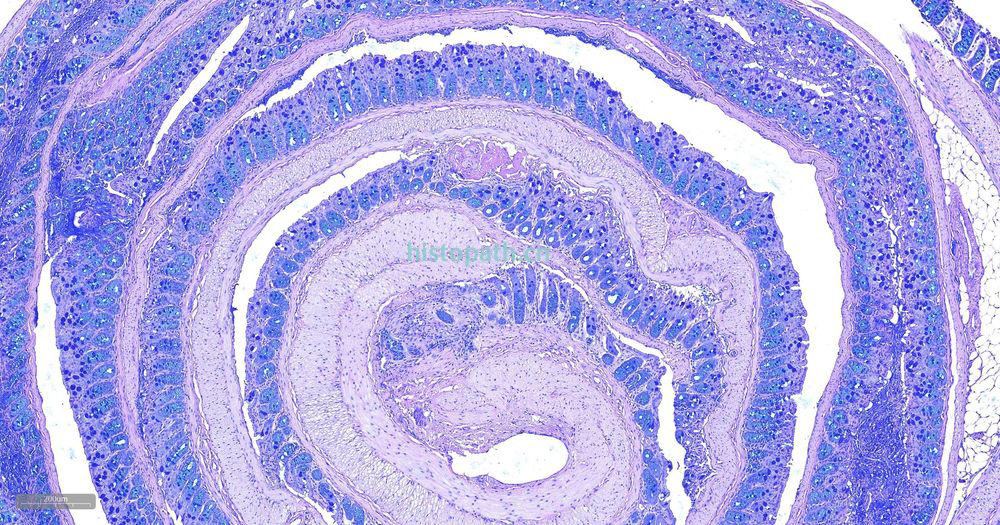

糖原染色是病理学中常规的染色方法之一,该法常用来显示糖原和其他多糖,该染色液不仅能够显示糖原,还能显示中性黏液性物质和某些酸性物质。

阿利新蓝和PAS技术联合使用可鉴别同一组织切片中的中性黏蛋白和酸性黏蛋白。这种技术也常用作广泛检测黏蛋白的手段。阿利新蓝可将唾液黏蛋白、硫黏蛋白和蛋白多糖染成蓝色。PAS技术可将中性黏蛋白染成深红/红紫色,同时将既含中性黏蛋白有含酸性黏蛋白的组织和细胞染成深浅不同的紫色,这是由于阿利新蓝与 Schiff试剂结合并反应。上述染色常可出现在含有中性黏蛋白和唾液黏蛋白的小肠杯状细胞中。

阿利新蓝是类铜钛花青染料,这种阳离子染料与酸性基团结合,也即阿利新蓝与组织内含有的阴离子基团如羧基和硫酸根形成不溶性复合物。分子中带正电荷的盐键与酸性黏蛋白多糖物质中带负电荷的酸性基团结合形成不溶性的复合物而呈蓝色,再与PAS进行复合染色,就能显示三种不同黏液物质成分。

染色结果: